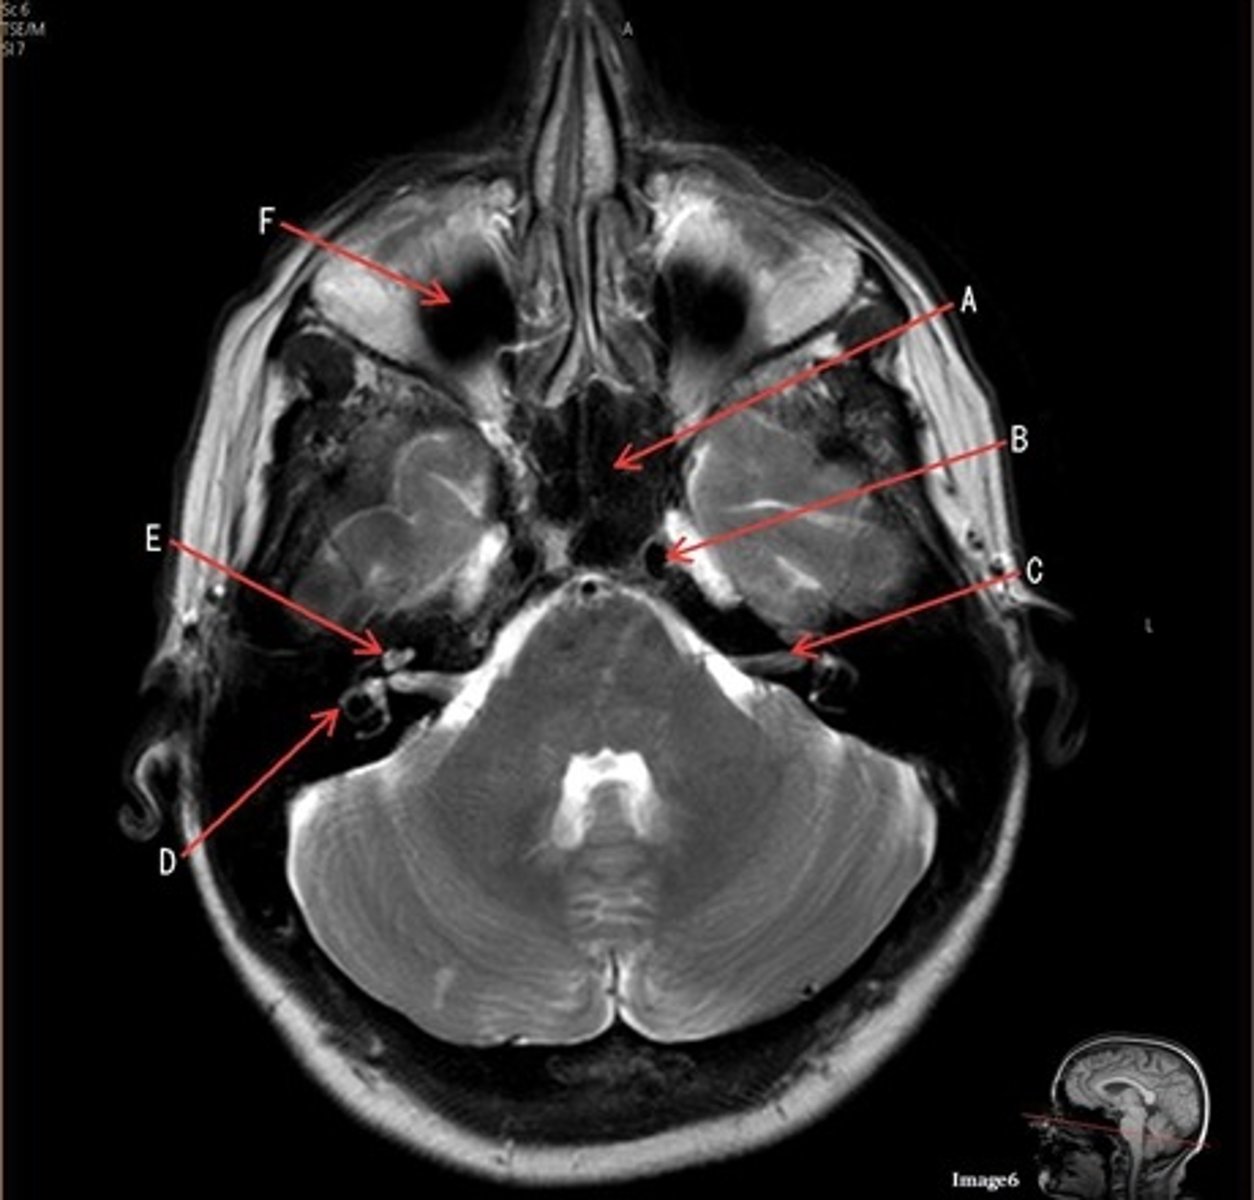

C

C- 7th cranial nerve, facial nerve

D

D. semi-circular canal

E

E- cochlea

F

F- maxillary sinus

letter A

anterior cerebral artery

letter C

7th cranial nerve- facial

8th cranial nerve vestibulocochlear on other side (posterior) of semicircular canal

letter F

medulla oblongata